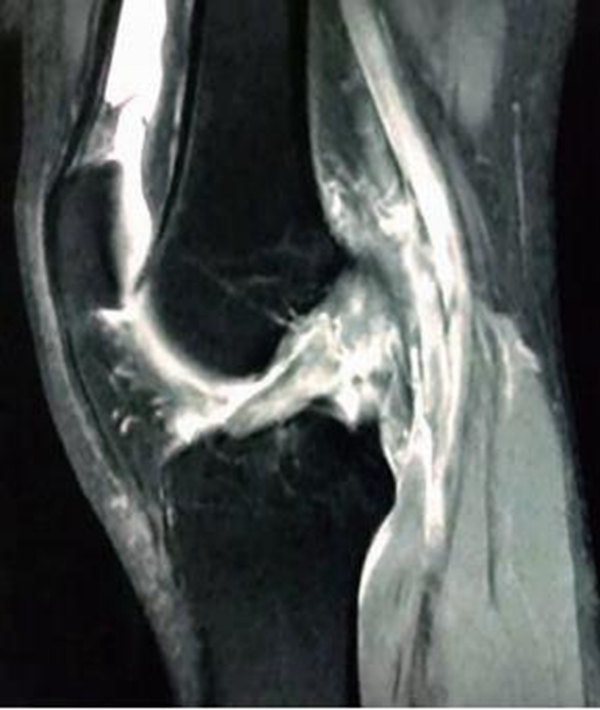

MRI检查不可作为ACL断裂的唯一诊断标准,临床上有部分ACL断裂后残端移位不明显,而是以瘢痕黏附于PCL或股骨髁的内侧面(图9)。该类情况需要临床医生对正常ACL的影像有清晰的认识,可以通过冠状位和矢状位上ACL的方向和角度来辨别,更重要的是与临床体格检查及病史三者结合以诊断。

图9 ACL断裂后断端移位不明显的MRI影像